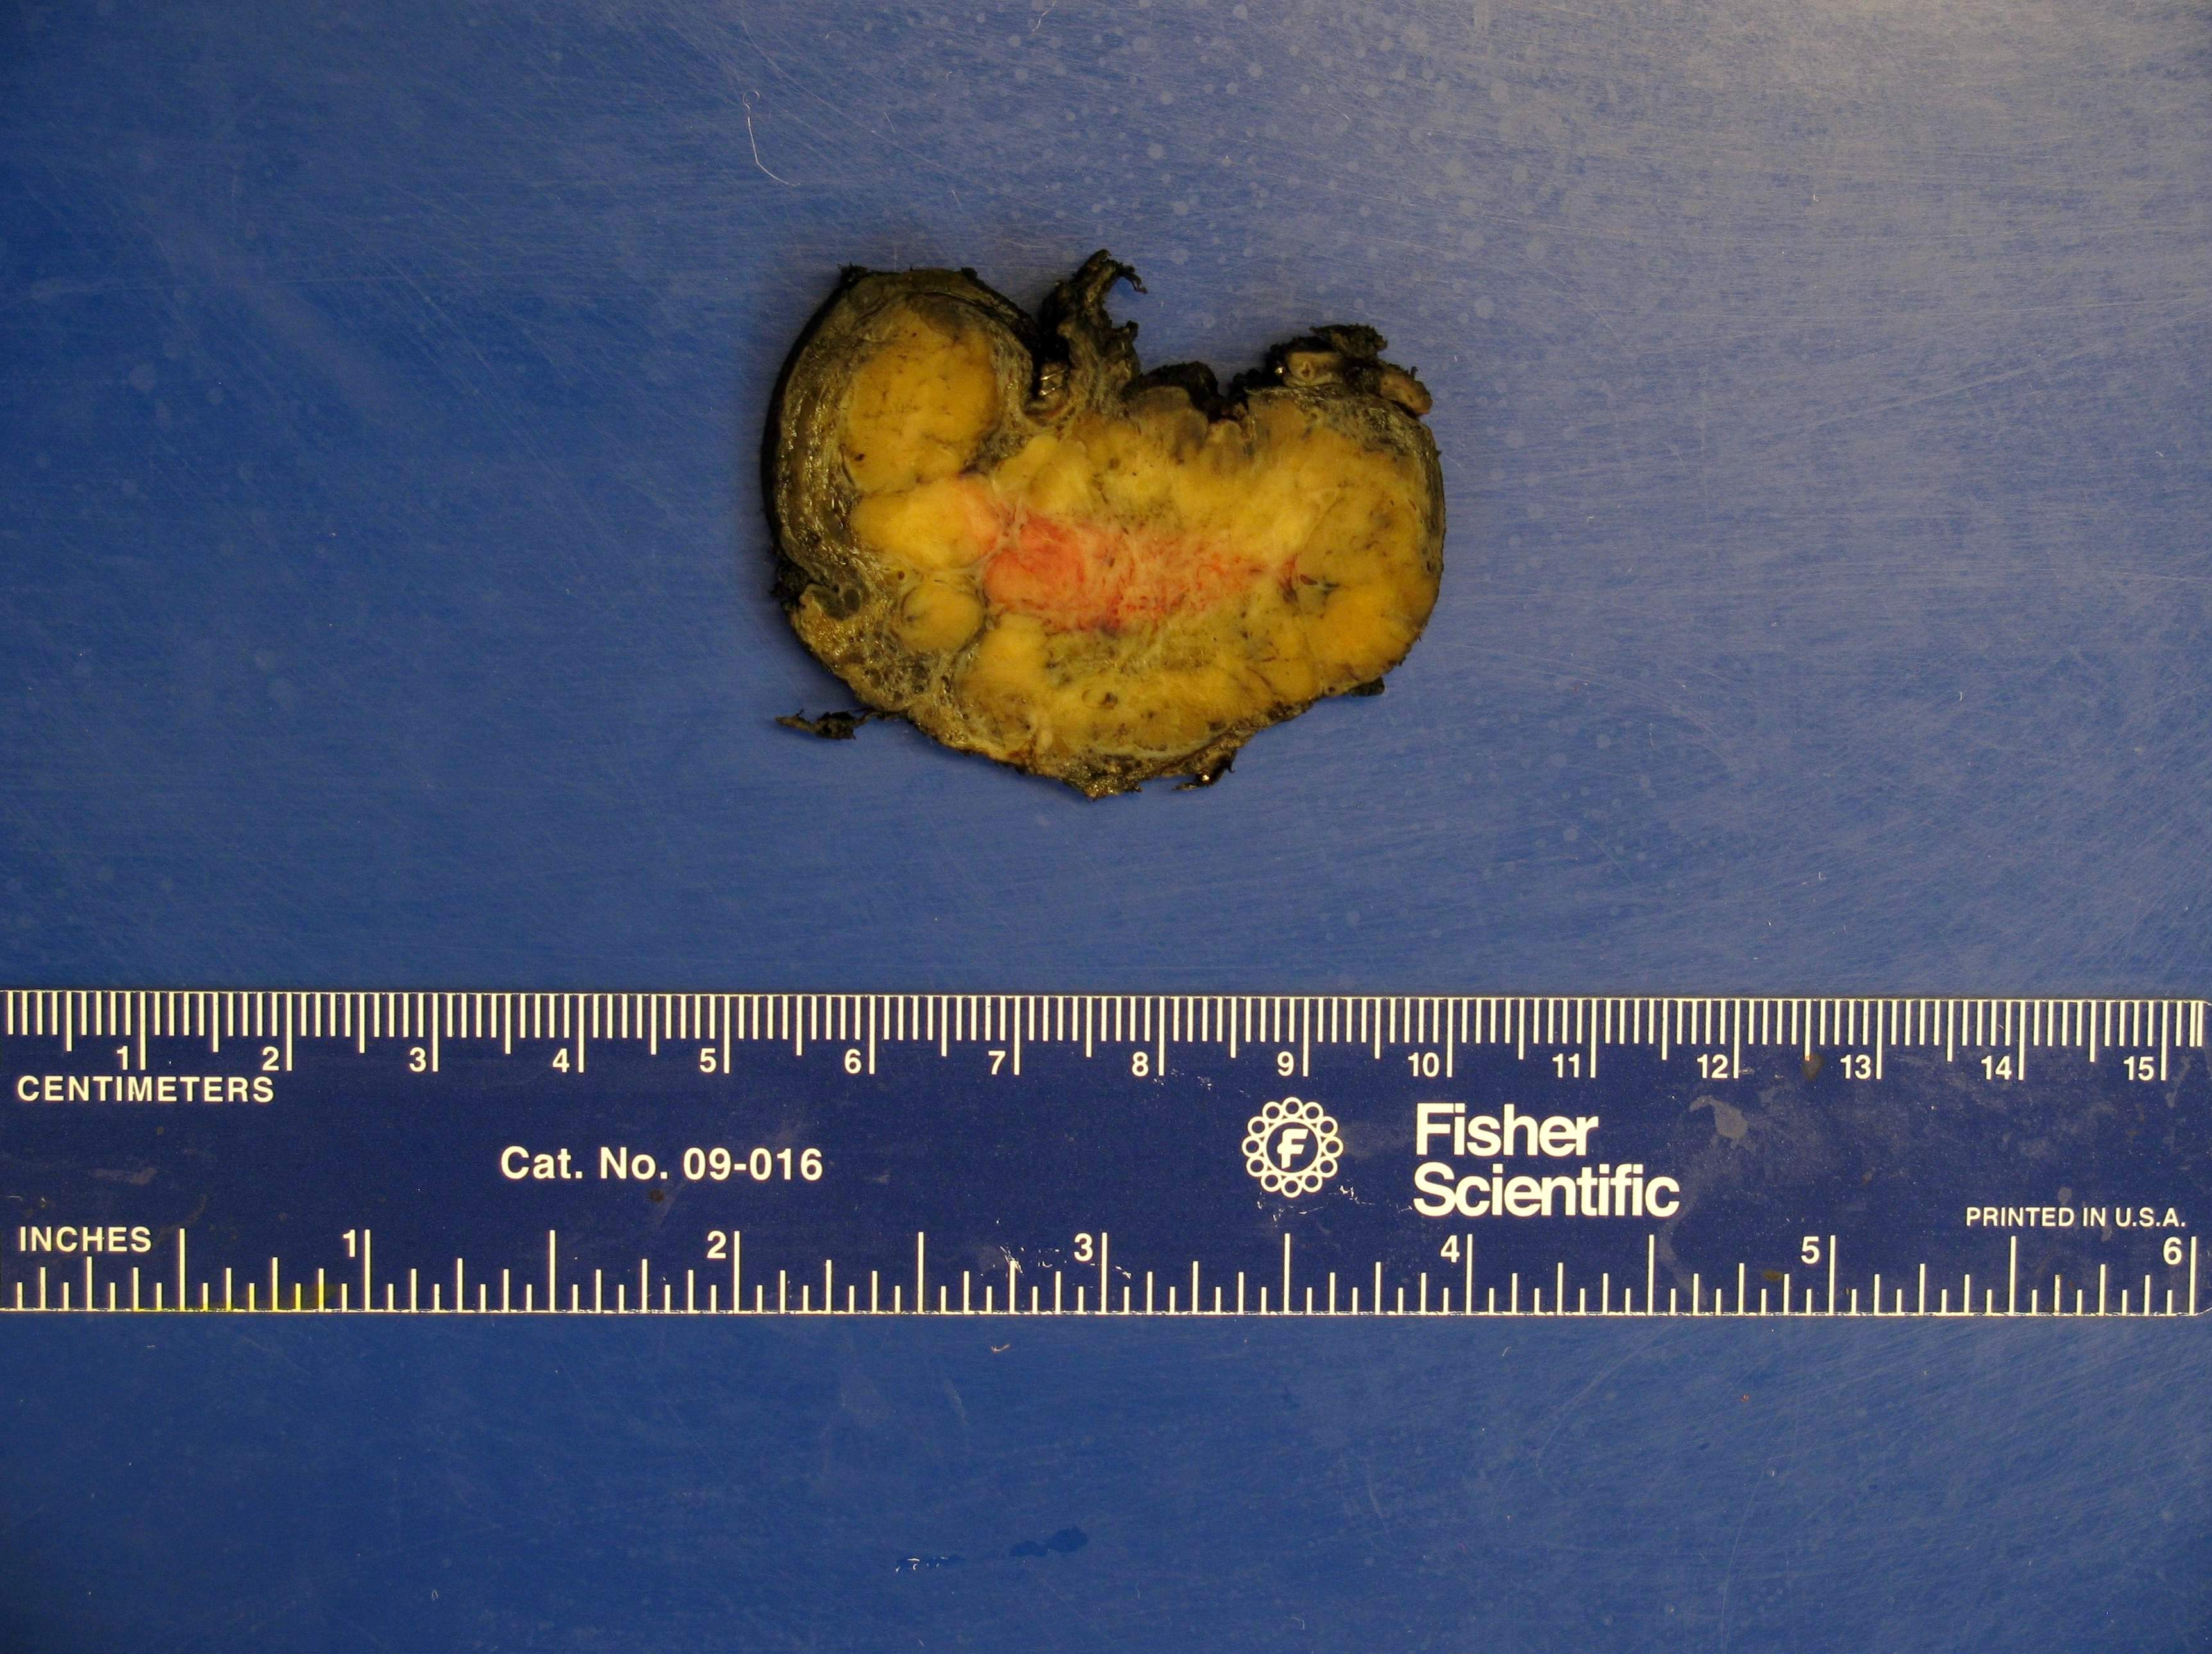

Gross description

- Firm, well circumscribed to infiltrative and partially encapsulated or pseudoencapsulated (Mariani-Costantini: Carotid Body and Vagal Paragangliomas - Epidemiology, Genetics, Clinicopathological Features, Imaging, and Surgical Management [Accessed 4 November 2021])

- Varies from dusky brown to red, gray or tan cut surface (J Radiol Case Rep 2019;13:19)

- Hemorrhage and cystic degeneration may be present

Gross images